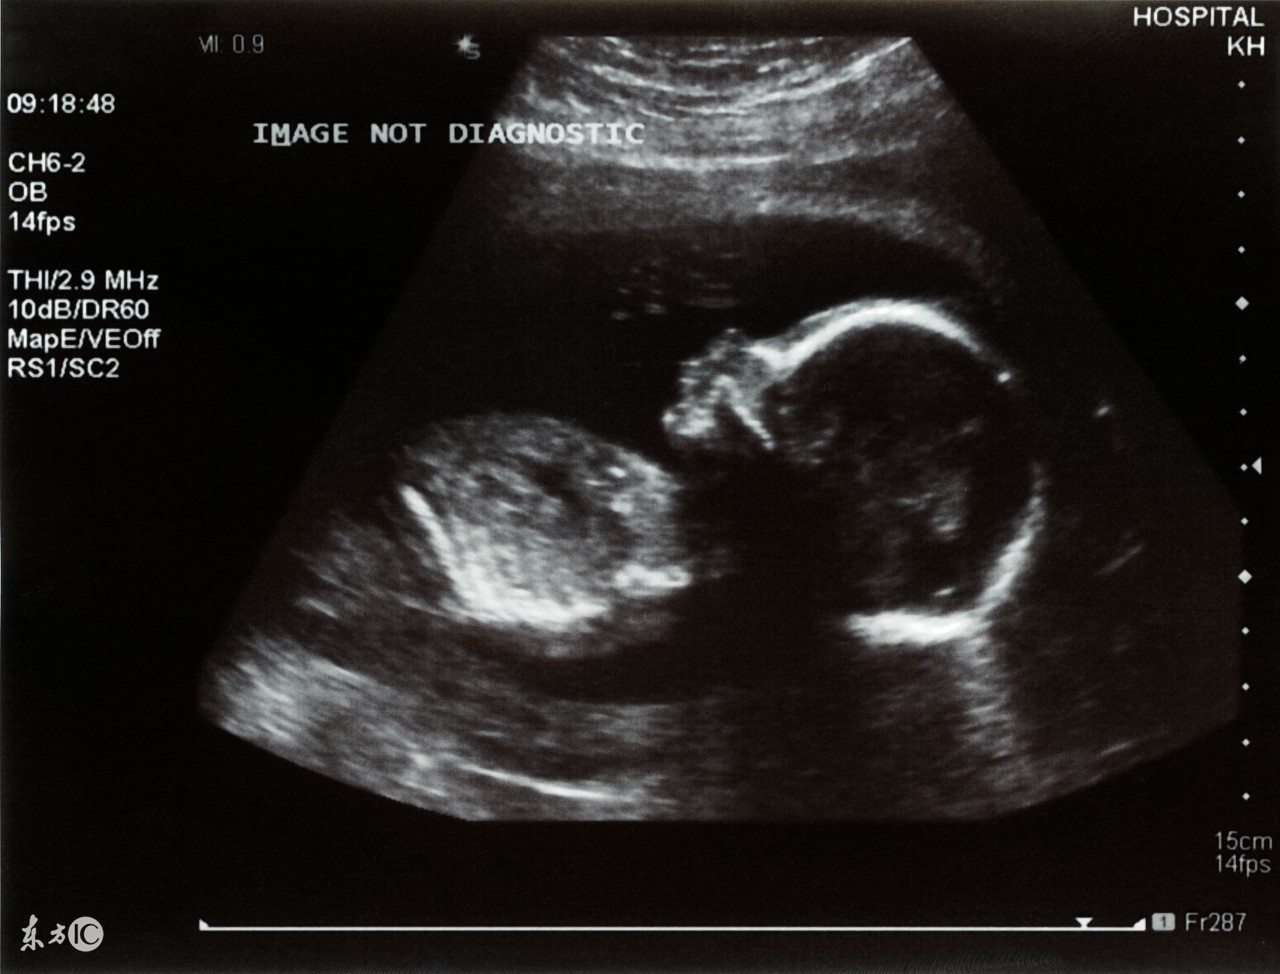

1、普通B超:也有人称为“黑白超声”,医学上称为二维超声、黑白色;

4、二维彩超:黑白色、分辨率比黑白超声高,会用彩色标注心脏、血流等指标;